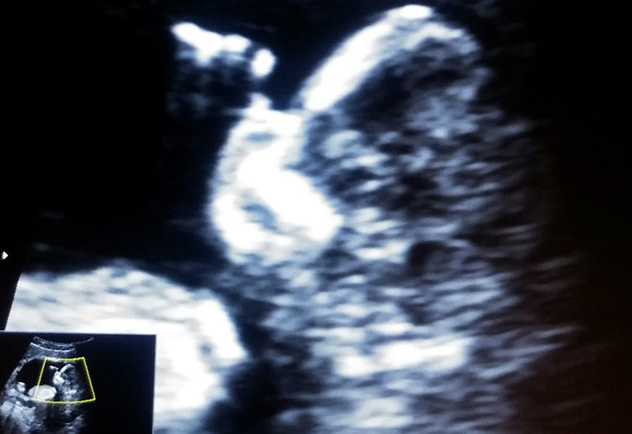

В 8 недель на УЗИ я первый раз увидела тебя, ты была похожа на маленькую бусинку.

Было 12 недель, когда я второй раз тебя увидела, ты уже была похожа на маленького человечка, который держал руки у лица.